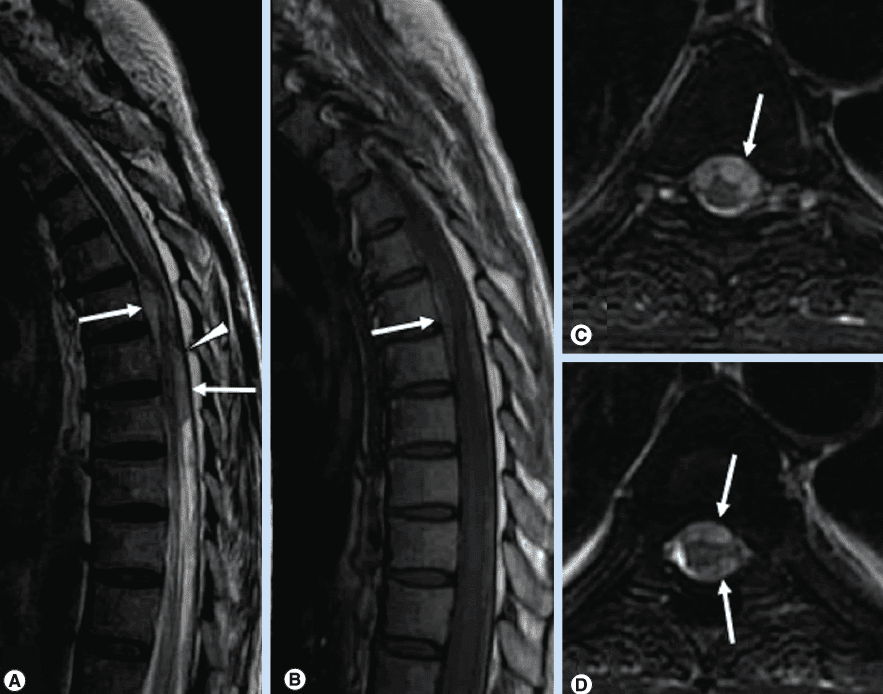

Ранняя диагностика БП затруднительна, благодаря сходству на ранних стадиях с эссенциальным тремором, мультисистемной атрофией и прогрессирующим надъядерным параличом. МРТ в диагностике паркинсонизма до недавнего времени рассматривалась в основном с точки зрения исключения или подтверждения заболеваний, вызывающих вторичный паркинсонизм - опухолей, субдуральных гематом, сосудистого поражения мозга, гидроцефалии. Чтобы дифференцировать болезнь Паркинсона от других заболеваний врачи проводят МРТ головного мозга.

Ряд последних специальных МРТ-исследований показал связь деменции и когнитивных нарушений у больных Паркинсоном с объемными изменениями в черной субстанции, ядре Мейнерта, гиппокампе, а также снижение общего церебрального объема. На данный момент считается, что признаками болезни Паркинсона на МРТ снимках станет:

- атрофия черной субстанции, бледного шара и хвостатого ядра

- зона изменённого МР-сигнала, гиперинтенсивного на Т2-ВИ и FLAIR-ИП, слабо гипоинтенсивного в Т1-ВИ, повышения МР-сигнала на DWI.

Показывает ли МРТ болезнь Паркинсона

Поскольку единой точки зрения о причине развития данного заболевания пока в медицине нет, то его точная диагностика и лечение - весьма затруднительная задача. Здесь важную роль играет и детальный сбор анамнеза, и результаты аппаратных методов сканирования мозга. При подозрении на болезнь Паркинсона МРТ головного мозга следует проводить на высокопольном томографе мощностью не менее 1,5 Тесла. В ходе обследования МРТ покажет зоны аномального функционирования и анатомического строения. Прямых, явных признаков недуга врач-рентгенолог не увидит, однако есть характерные поражения черной субстанции мозга, которые очень часто отмечаются при данном заболевании. При болезни Паркинсона МРТ головы в первую очередь проводится для исключения других вероятных причин симптомов: